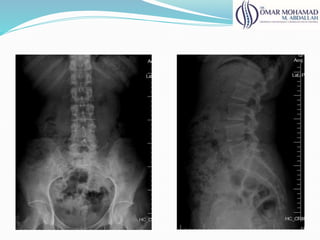

RX

● RX normal em paciente com lombalgia

● 46% achados acidentais

● Baixa correlação entre dor lombar e os achados de

exame

RX ● RX normalem paciente com lombalgia ● 46% achados acidentais ● Baixa correlação entre dor lombar e os achados de exame